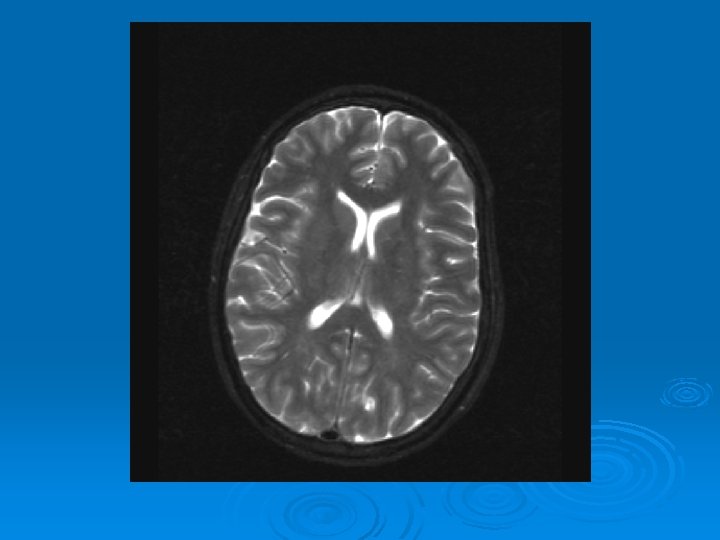

MRI: 2/9/2007 Ø 1. Leptomeningeal enhancement, most prominently seen over the posterior parietal and occipital lobes.

CMV: Ventriculoencephalitis Ø Clinical: Can have abrupt presentation of confusion, apathy, impaired memory, withdrawal, nystagmus, motor weakness, cranial nerve deficits, ataxia, seizures, coma. Can rapidly progress. Ø Labs: CSF: Monocytic Pleocytosis, Low Glucose CMV PCR Positive in CSF: (Sensitivity, Specifity 80, 90%, PPV, NPV, 86 -92, 9598%) Serum CMV viremia Ø Ø Ø MRI: Subependymal enhancement, diffuse hyperintense T 2 WI, ventriculomegaly.

MRI of CMV patient Magnetic resonance images of a patient with cytomegalovirus ventriculitis Ependymal enhancement after injection of gadolinium. DPTA seen on coronal T 1 -weighted image. Ø Highly abnormal ependmal signal on proton densityweighted image of the brain in axial section. Ø Ø See images in: l Arribas et al, Cytomegalovirus Encephalitis, Annals of Internal Medicine, 1996, Vol 125, Issue 7